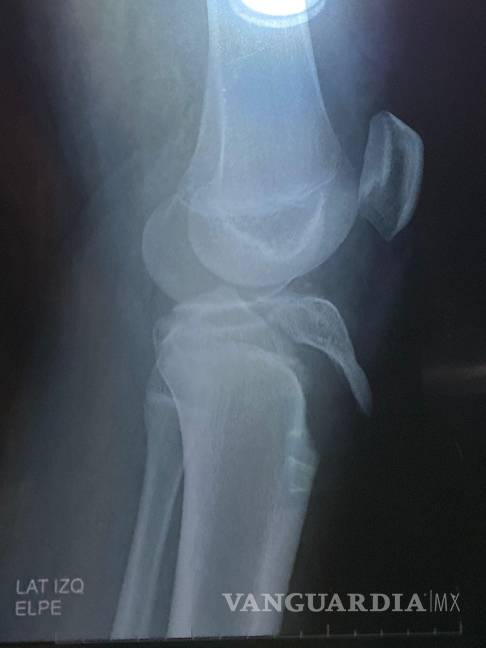

El menor participaba en prácticas para una actividad llamada “olimpiada” cuando resultó con una grave lesión en la rodilla que requirió cirugía para la colocación de tornillos.

$!La cirugía del estudiante implicó la colocación de tornillos en la tibia, costos que inicialmente cubrieron los tutores.

De acuerdo con la madre del alumno, la institución no llamó a una ambulancia ni siguió los protocolos establecidos para atención médica de emergencias. El estudiante fue entregado a su padre con la pierna manipulada y sentado en la recepción del colegio, sin que se contara con asistencia profesional inmediata, lo que pudo haber agravado la lesión.